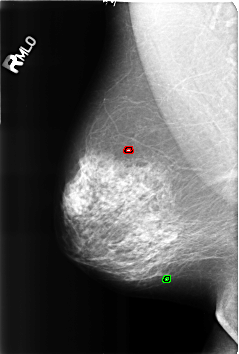

B_3220_1.RIGHT_MLO

RIGHT_MLO LINES 4600 PIXELS_PER_LINE 3104 BITS_PER_PIXEL 12 RESOLUTION 50 OVERLAY

FILE: B_3220_1.RIGHT_MLO.OVERLAY

TOTAL_ABNORMALITIES 2

ABNORMALITY 1

LESION_TYPE CALCIFICATION TYPE LUCENT_CENTER DISTRIBUTION N/A

ASSESSMENT 2

SUBTLETY 5

PATHOLOGY BENIGN_WITHOUT_CALLBACK

TOTAL_OUTLINES 1

BOUNDARY

ABNORMALITY 2